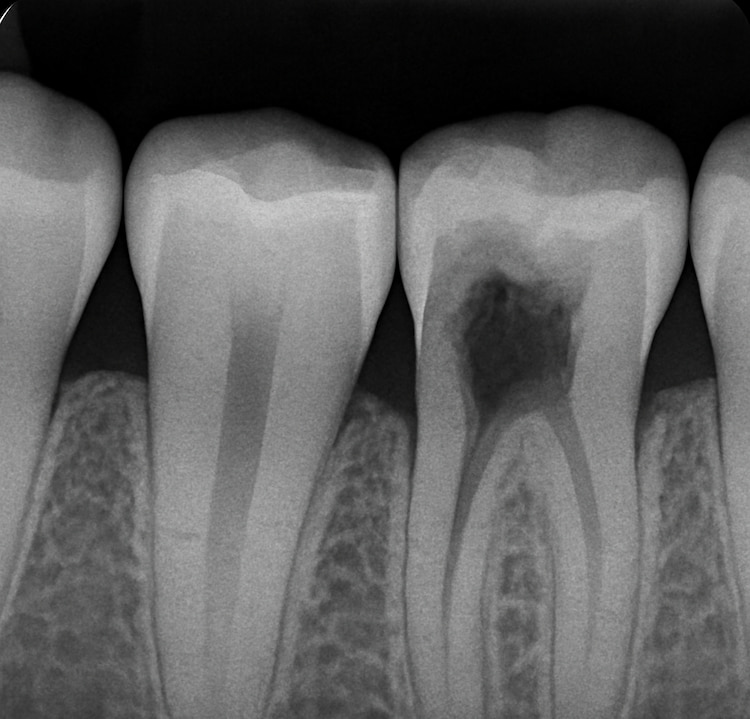

4. Pulp Damage

Tooth decay can penetrate a tooth’s nerve (pulp) without repair. Symptoms, such as a very painful, swollen area, can develop. By this point, the infection may permit a root canal treatment or tooth extraction.

When decay reaches the inner part of your tooth (the pulp), it can cause pain and infection. In a root canal, the dentist removes the infected pulp, cleans the inside of the tooth, and seals it. A crown is often placed afterward to strengthen the tooth.

Tooth pain isn’t always from a cavity, but if it worsens when you eat something sweet, hot, or cold, decay could be the cause. At Langley Dental Group, we use digital X-rays and advanced diagnostic tools to pinpoint the exact reason for your discomfort, whether it’s a cavity, enamel wear, or gum sensitivity.